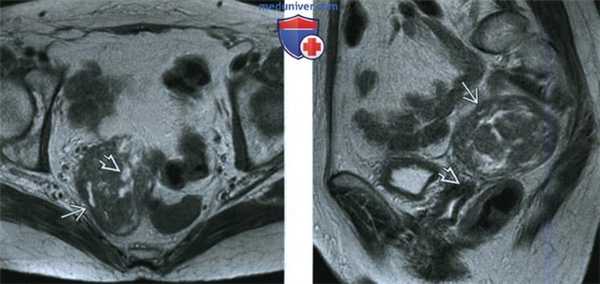

(Слева) При МРТ на Т2-ВИ в аксиальной плоскости у пациентки 62 лет, которой 5 лет назад была выполнена лапароскопическая гистерэктомия в сочетании с двусторонней сальпингоофорэктомией, а незадолго до исследования был диагностирован рак толстой кишки в ранней стадии, выявлено объемное образование в правой половине малого таза. Образование в основном солидное и по сравнению с мышцами таза дает более интенсивный сигнал, обусловленный кистозным компонентом.

(Справа) При МРТ на Т2-ВИ в сагиттальной плоскости у той же пациентки видно объемное образование В в малом тазу, расположенное непосредственно над культей влагалища и не связанное с ней.

(Слева) При МРТ на Т2-ВИ в аксиальной плоскости у пациентки 45 лет с диагностированной миомой матки, которой ранее была выполнена лапароскопическая миомэктомия, выявлено объемное образование в правой половине малого таза, дающее гомогенный сигнал низкой интенсивности. Имеются трубчатые сосудистые структуры - участки потери сигнала из-за протекающей по ним крови. Они отходят от брыжейки и кровоснабжают объемное образование.

(Справа) При МРТ с контрастированием на Т1-ВИ FS в аксиальной плоскости у той же пациентки видно, что объемное образование неравномерно усиливает сигнал и на его левой стороне заметны зоны отсутствия сигнала, обусловленные небольшими сосудами.